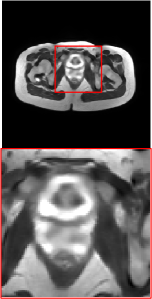

Figure 5 provides the qualitative comparison of the various methods on the four datasets at a scale of 4. The top, second, third, and bottom rows are the SR results under the FastMRI, clinical brain, clinical tumor and clinical pelvic datasets, respectively. The red boxes indicate the zoom-in region of complicated anatomical structures along with their corresponding error maps. Note that the brighter textures in the error maps, the lower the quality of the reconstructed images. As can be seen, compared to methods based on Transformers and CNNs, diffusion-based methods like DisC-Diff and DiffMSR (Ours) are capable of reconstructing high-realistic images with promising reconstruction metric scores (PSNR and SSIM). Nevertheless, while DisC-Diff can reconstruct high-precision MR images, it does not preserve the structure present in the original HR images, introducing some additional information that can affect medical diagnosis. In contrast, our method combines DM and PLWformer, which can preserve the original image’s structure while restoring high-frequency information.

In this section, we present more visual qualitative comparisons. Figures 8, 9, 10, and 11 show the reconstruction results of each method in FastMRI, clinical brain, clinical tumor, and clinical pelvic, respectively. As can be seen, although DisC-Diff can reconstruct MR images with high-frequency information, it fails to preserve the structure and content of the original Target HR image effectively, resulting in image distortion. In contrast, our proposed DiffMSR can restore high-frequency information while preserving the structure of the original HR image, indicating the effectiveness of the joint use of DM and PLWformer.